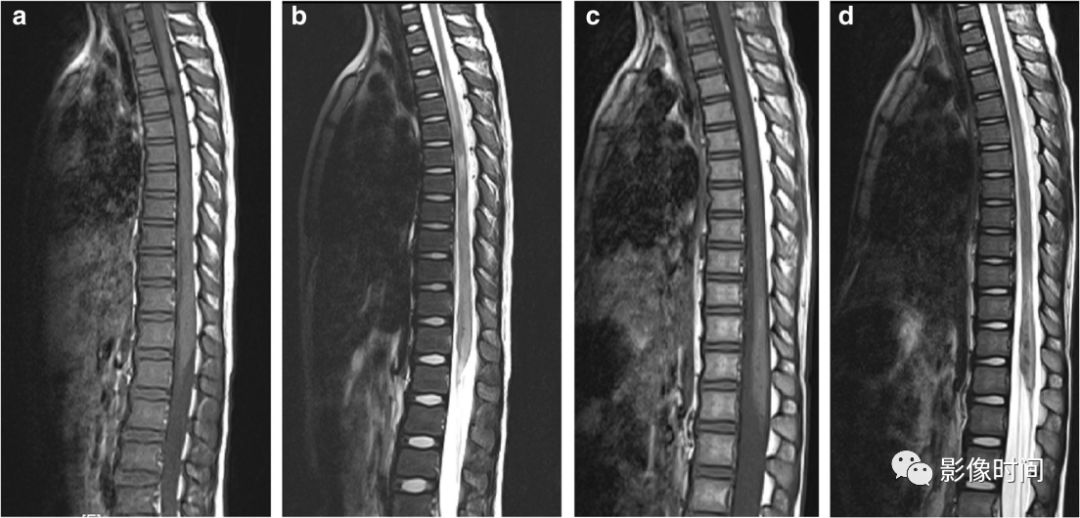

硬脊膜动静脉瘘 (spinal dural arteriovenous fistula,SDAVF):供应脊膜或神经根的细小动脉,在椎间孔处穿过硬膜与脊髓引流静脉相通,导致脊髓回流受阻。病因不明,成人-老年人胸腰段多见,缓慢起病,进行性加重。

MRI:

-

矢状位 T2WI 发现长节段高信号

矢状位 T2WI 脊髓周围流空低信号血管影

部分可见强化,提示血脑屏障破坏

脊髓内长节段T2WI高信号,髓周可见多发点状流空血管,增强扫描出现强化